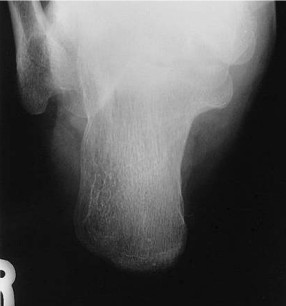

What is the correct CR angle and centering point for this projection?

CR 40 degrees cephalad from long axis of foot (40 degrees from vertical if long axis of foot is perpendicular to IR), CR to base of third metatarsal to emerge at a level just distal to lateral malleolus

Discuss the correct anatomy demonstrated on this image

entire calcaneus should be seen from tuberosity posteriorly to talocalcaneal joint anteriorly

What is in profile on this image?

susentaculum tali is in profile medially

What indicates on this image that the CR angle was correct?

open talocalcaneal joint space